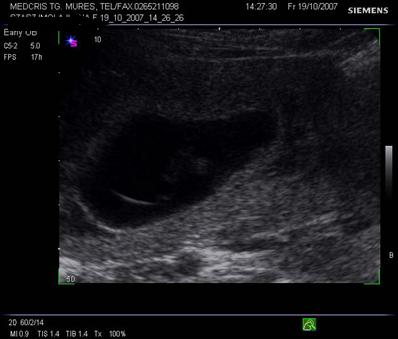

Fig. nr.205. Placenta fundica si posterioara ( normal inserata, cu sageata ) la o sarcina de 16 sapt.